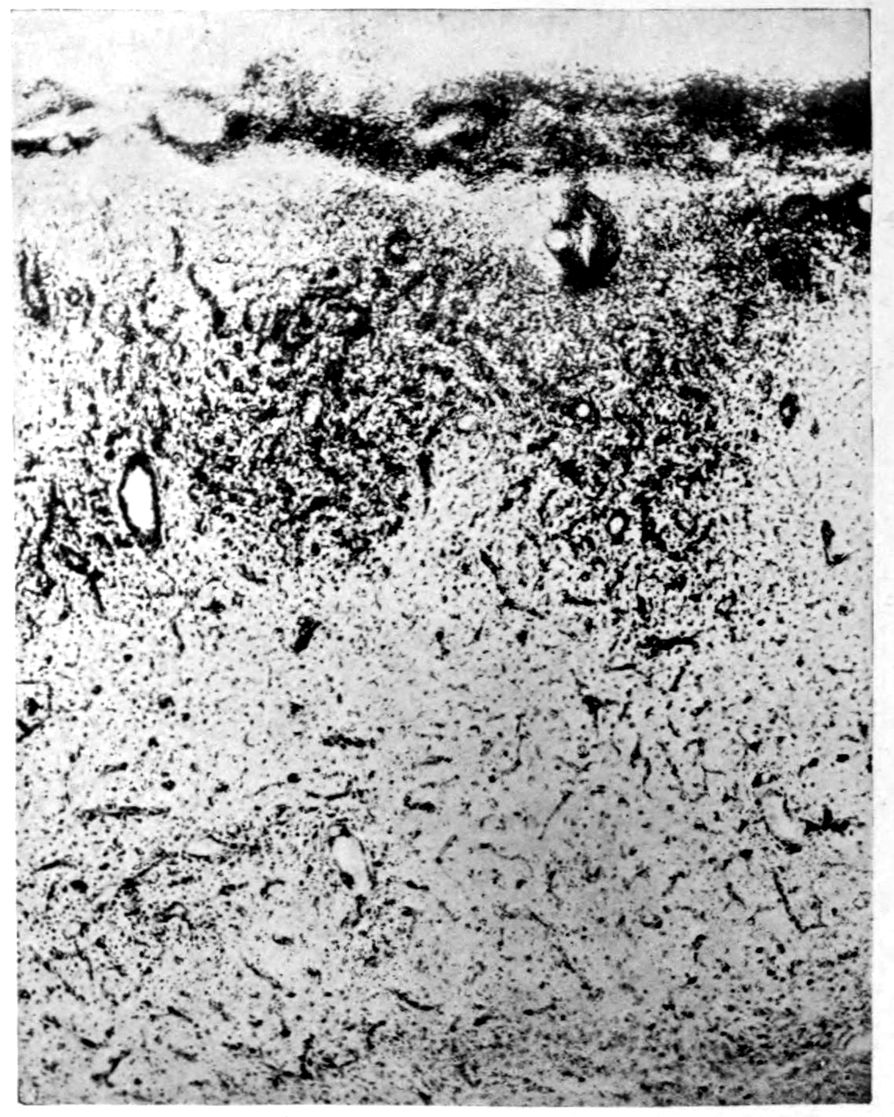

The calvarium was dense and the dura mater thick and adherent. There was a chronic leptomeningitis, which, however, was rather unusual in being most marked in the posterior cisterna and along the sulci of the cerebellar hemispheres. There was a general cerebral sclerosis, with a question of atrophy of the superior temporal gyri (suggesting the so-called Lissauer’s paresis). There was a marked cerebellar sclerosis with a consequent sclerosis (grossly palpable) of the commissural fibres of the pons. There was a generalized slight spinal sclerosis. As a fair sample of the variety of head findings in paretic neurosyphilis, the details of the head examination are presented.

39Crown bald, with a slight fuzzy growth of short hairs. Scalp slightly adherent to calvarium; latter of usual thickness but denser than normal. Dura adherent to calvarium in region of vertex; dura not remarkable. Sinuses normal. Arachnoid villi moderately developed. Pia mater a trifle thickened and rather evenly throughout the cerebral portion. Linear sulcal markings are remarkable for their absence. The wall of the cerebellomedullary cisterna is thick and opaque. The most prominent pial thickenings are over the cerebellum. These are linear or may show feathery out-growths and are seated over the sulci, particularly in the neighborhood of the fissure and about the great cerebellar notch. They correspond fairly well with the focal variation in consistence of underlying tissues noted below.

Brain weight, 1265 grams. Consistence somewhat increased throughout and somewhat evenly increased. The prefrontal region shows the maximal increase of consistence but the remainder of the frontal region and corresponding occipital region are much firmer than normal. The two superior temporal gyri appear to be firmer than adjacent gyri and are possibly slightly diminished in superficial diameter. The hippocampal gyri are fairly firm. The substance on section is a trifle more moist than normal. The gray and white matter cut quite evenly. Diminution in depth of gray matter, if existent, could not be demonstrated. The ventricles show a moderate sanding throughout, best marked in the fourth ventricle. The basal ganglia are not remarkable except for the development of numerous dilated perivascular spaces about the lenticulostriate vessels. The pons is atrophic, but more so on the right side. The pons, like the prefrontal cortex, shows on section a distinct increase of consistence immediately beneath the pia mater. The white bands of the pons on section are distinctly firmer than the intervening substance. The olives are of equal consistence. Weight of cerebellum, pons, and medulla, 155 grams. The cerebellum shows an obvious atrophic and gliotic process of a symmetrical character. The superior surface, including both vermis and hemispheres, shows a consistence above normal and general reduction of the depth measured from the white matter. The reduction in depth gives rise to a visible depression as compared with tissue posterior to the postclival sulci. The lobus cacuminis, though slightly raised from the surrounding lobes, is equally firm, if not firmer. The superior and inferior surfaces show practically an equal increase of consistence. The dentate nuclei are not especially increased in consistence. The flocculi are reduced in size about one-third.

Microscopic findings are here presented merely in sufficient detail to establish the diagnosis. The left superior frontal gyrus shows extensive and somewhat irregular cellular and fibrillar gliosis of the plexiform layer, together with an increase of thickened vessels having lymphocytes and plasma cells in their sheaths.

The perivascular infiltrations are most extensive in the lower layers of the cortex. The lamination is in places thoroughly obscured, except that representatives of the layer of large external pyramids are almost always demonstrable.

The layer of medium-sized pyramids has undergone more numerical loss of elements than have the other layers.

Gliosis of white matter.

Specimens from the cerebellum show a destructive process of great severity, but a little irregular in extent, affecting chiefly the Purkinje cell belt. The Purkinje cells are often absent throughout one side of a given lamina, and there has ensued a dense accumulation of neuroglia cells along a former Purkinje cell belt, together with a considerable gliosis of the molecular layer. Considerable gliosis of the white matter, both diffuse and perivascular in distribution.

Perivascular plasma cell infiltrations as in cerebrum, but largely meningeal or in the white matter.

41Characteristic and constant in paretic neurosyphilis is the Plasmocytosis and Lymphocytosis, Perivascular in distribution about small cortical vessels. There is also a characteristic (though characteristically less prominent) Plasmocytosis and Lymphocytosis, Meningeal in distribution. The pleocytosis of the spinal fluid, almost constant though variable in amount in life, is an indicator of the meningeal picture and less directly of the parenchymatous picture.

Granular Ependymitis (“sanding” of ventricle floors) is characteristic and may be regarded as part of the parenchymatous picture. This ependymitis is an indicator how chemical changes could be readily produced at least in the ventricular fluids, since the limiting membranes of the nerve tissue are here subject to multiple breaks. The “sanding” is a neuroglia reaction to these multiple small breaks (Weigert’s explanation).

Parenchymatous losses have led to Atrophy and Sclerosis, of very varying extent in different parts of the encephalon. The atrophy is characteristic in paretic neurosyphilis, but by no means constant. Numerous cases have come to autopsy without clearly defined gross atrophy. Sclerosis is also characteristic and even more frequent than atrophy, doubtless because sclerosis represents an earlier phase of a process eventuating in gross atrophy.

A Tabetiform Picture characterizes the spinal cord, but in this case the tabetic clinical picture did not precede the paretic clinical picture. We are consequently to regard the tabetic spinal process as incidental and on all fours with the Cerebellar and Pontine Atrophy.